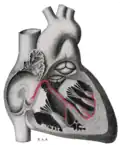

![]() Sinoatrial node shown at 1. The rest of the conduction system of the heart is shown in blue. | |

Additional images

-

Heart; conduction system (SA node labeled 1) -